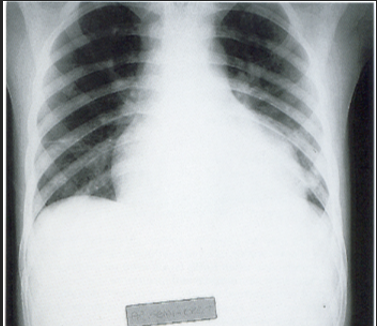

She had been healthy until 2 months ago, when she was hospitalized for 48 ...

infection with mild respiratory distress and poor fluid intake.